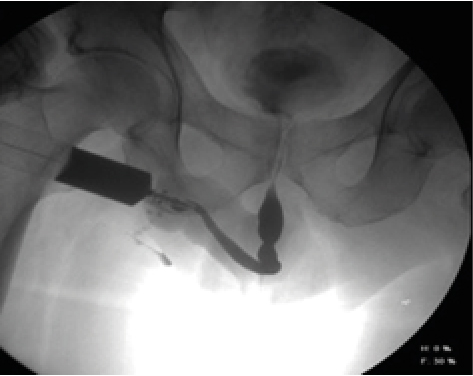

The identification of the anatomical portions of the urethra by retrograde urethrography is part of the learning process of the radiologist technician and medical resident in radiology, which seems easy and yet they are part of daily errors (Figure 4,5,6), it consists the penile urethra, bulbar, bulbomembranous, membranous, urogenital diaphragm, prostatic and verumontanum [2].

Figure 6: 63-Year-Old Male with a History of Prostatic Tran’s Urethral Resection, Which Presented Difficulty in Urination, Was Diagnosed by Image as Posterior Bulbar Stenosis and by Cystoscopy was Anterior Bulbar Urethral Stenosis